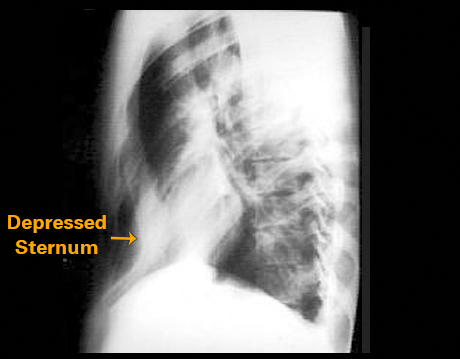

Your choice: Pectus excavatum

This lateral chest X ray shows pectus excavatum, a thoracic deformity affecting the sternum. This view demonstrates depression of the lower portion of the sternum causing the distance between the posterior surface of the sternum and the anterior surface of the vertebral bodies to be decreased.